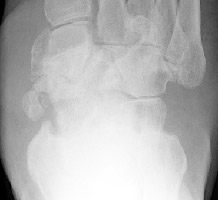

Charcot Joint: AP -Charcot Joint: Lateral - Disorganization of Chopart jointNEUROPATHIC JOINT DISEASE (CHARCOT JOINT) articular degeneration secondary to weight-bearing trauma and neurovascular changes on sensory deficient joint, resulting in bony resorption and formation.

Osteophytes, joint effusions, and soft tissue swelling are among the common early findings. Later in the disease process, acute fractures, dislocations, and subluxations may occur. Subluxations at the tarso metatarsal joints may mimic Lisfranc fracture/subluxations. Frequent fractures include subchondral fractures of the second metatarsal head, and avulsion fractures of the posterior calcaneal tubercle. Tapering osteolysis ("sucked candy" or "pencil-pointing"), bony fragmentation with well defined margins, and fusions with or without pseudoarthroses are other signs of progression.

Joint space narrowing and bony fragmentation may mimic early osteoarthritis. Osteophyte formation tends to be more aggressive than with osteoarthritis.